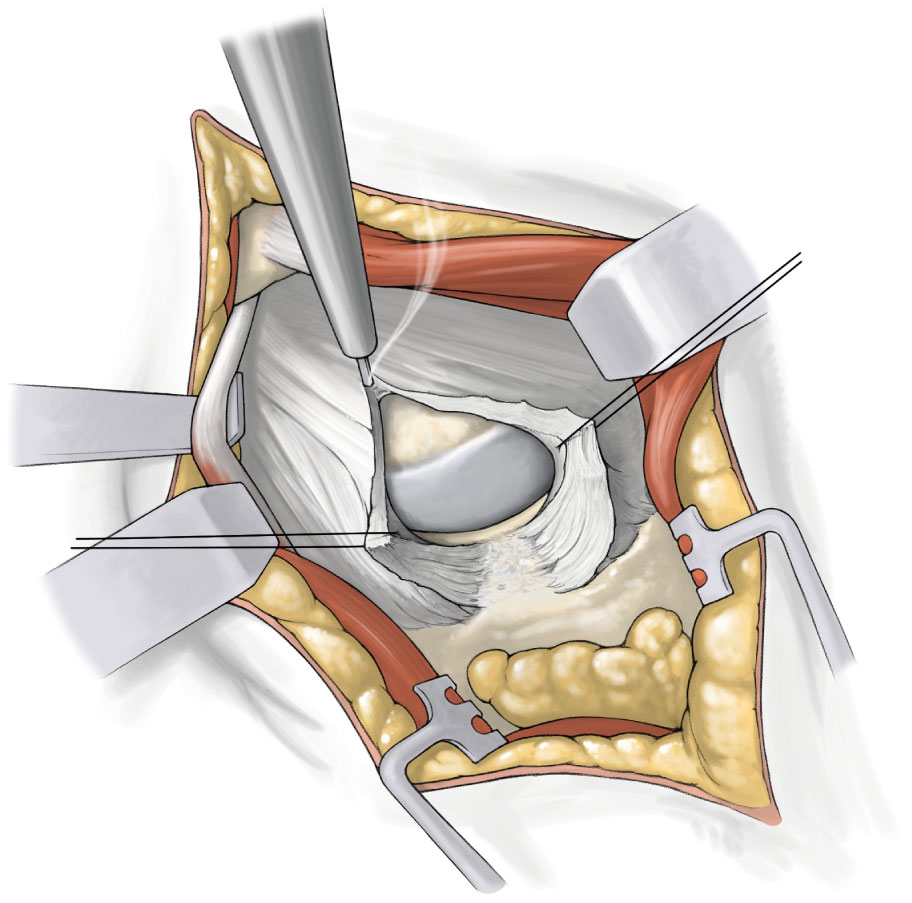

将患肢恢复至初始体位,准备处理髋臼侧。在髋臼的前方、后方,以两把带尖Hohmann置于关节囊和盂唇之间的髋臼窝中,切除盂唇和钙化组织,在切口近端髋臼边缘的关节囊下放置一个Zelpi牵开器,切口远端放置一个Romanelli牵开器,形成髋臼锉进入髋臼的通道,移除尖头Hohmann拉钩,用直角骨钩勾住髓腔锉,将股骨近端向前拉。

将对线手柄、导向器、带螺纹髋臼适配器和髋臼杯试模组合,并将其打入髋臼。